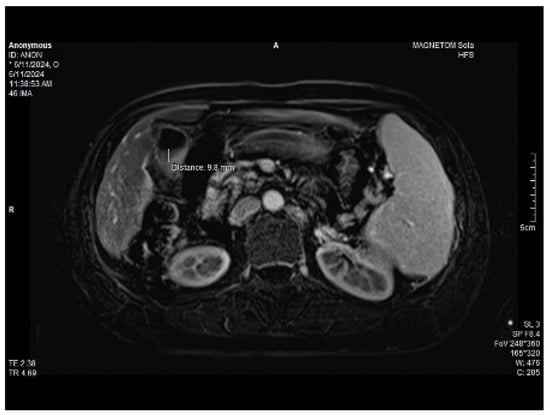

Abdominal MRI study confirmed the hepato-splenomegaly, ascites and the patency of the portal vein system. In addition, small veno-portal shunts were highlighted at the periphery of both hepatic lobes. Various MRI features are depicted in Figure 6, Figure 7, Figure 8 and Figure 9.

Figure 6. MRI featuring perihepatic and perisplenic ascites.

Figure 7. MRI: splenomegaly.

Figure 8. Massive thickening of the gallbladder wall, MRI features.

Figure 9. Small veno-portal shunts visible at the periphery of both hepatic lobes: MRI aspects.